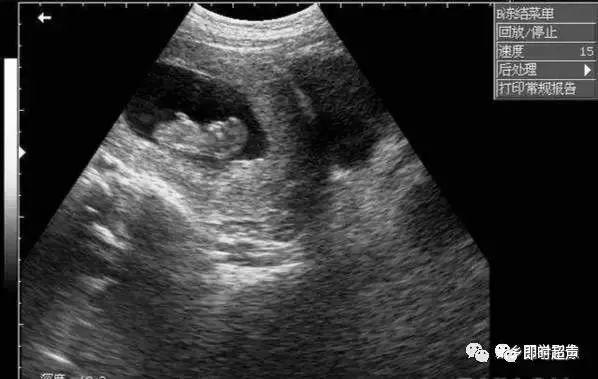

孕13周胎儿二维切面图及彩色血流图